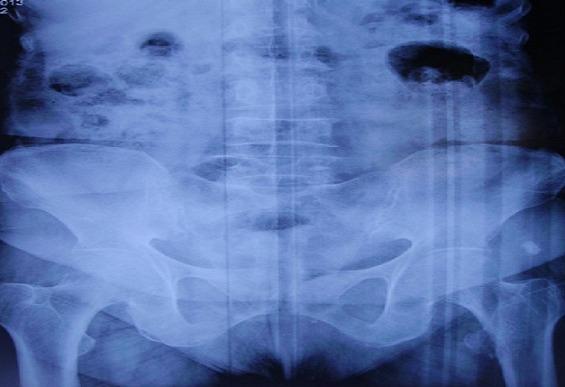

[Isolated fracture of the lesser trochanter in an adult, and if it was a metastasis: a case report and literature review].

https://cdn.ncbi.nlm.nih.gov/pmc/blobs/0b91/3996447/50aa60a1e0db/PAMJ-16-97-g001.jpg